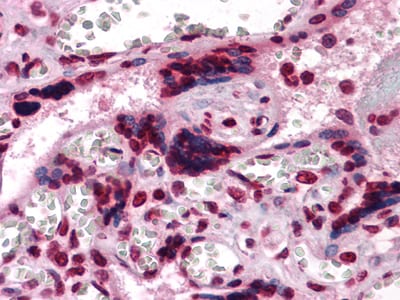

分类: 科研抗体货号: 30008别名: MCSF应用: IHC反应种属: Human